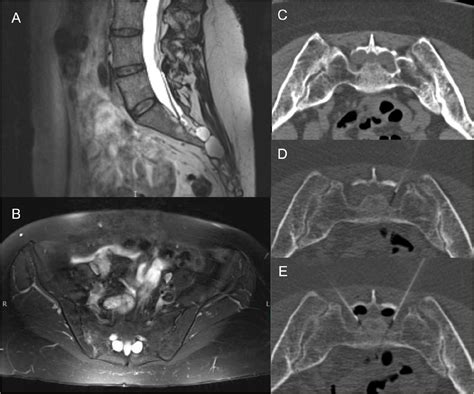

Diagnosing a symptomatic Sacral Tarlov Cyst requires a comprehensive approach. Because they are soft-tissue structures, they are best visualized using high-resolution Magnetic Resonance Imaging (MRI). A radiologist or neurosurgeon will look for specific markers, such as the location, size, and the degree of bone remodeling (erosion) occurring in the sacrum, which indicates that the cyst has been present for a significant period.

In addition to imaging, physicians may conduct a detailed neurological examination to map out sensory deficits and assess muscle strength. Some clinics may also utilize specialized imaging, such as a Cine-MRI, to study the flow of cerebrospinal fluid around the cyst.

Because these cysts often remain asymptomatic, they are frequently discovered incidentally during diagnostic imaging, such as an MRI or CT scan performed for an unrelated reason. However, when they grow in size or exert significant pressure on the surrounding nerves, they can lead to a variety of symptoms that mimic other spine-related conditions, making an accurate diagnosis essential.